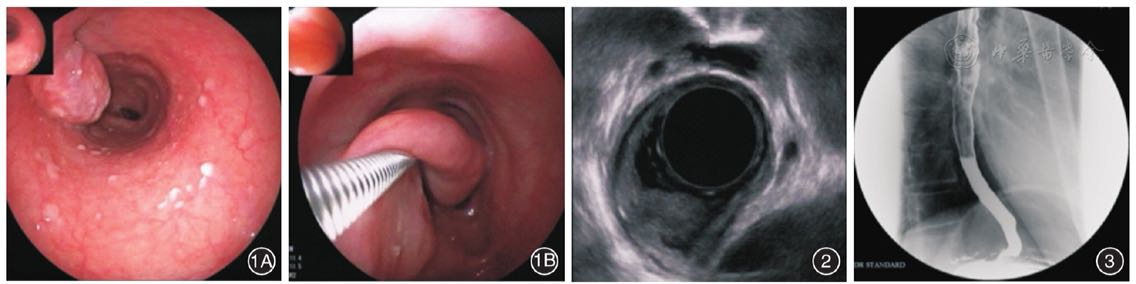

胃镜检查:食管距门齿约28 cm处可见一长蒂黏膜下隆起,活检钳触之可活动(图1)。超声内镜检查:食管病变处无回声改变,长蒂根部起源于黏膜下层(图2)。胸部CT平扫+增强:食管中段腔内软组织密度影,局部管腔狭窄,平扫CT值约为42 HU,增强后强化不明显。上消化道造影:食管中上段可见长条形泪滴状充盈缺损,上缘边缘欠清,余边界清晰;食管中段浅弧形凹陷,考虑外压性病变或黏膜下病变可能性大(图3)。

图1胃镜检查所见 1A:食管距门齿约28 cm处一长蒂黏膜下隆起;1B:活检钳触之可活动 图2内镜超声提示长蒂根部起源于黏膜下层,食管病变处无回声改变 图3上消化道造影见食管中段浅弧形凹陷,考虑外压性病变或黏膜下病变可能性大